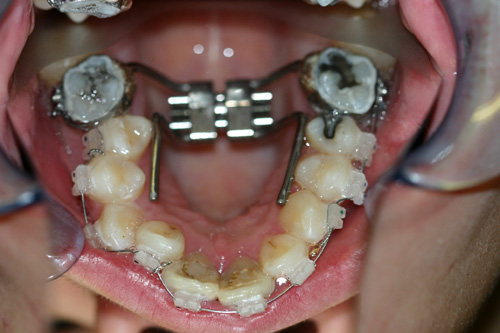

Rapid Maxillary Expansion Appliances

These appliances come in various designs. The patient is given a pen-sized wrench to do 1/4 turn per day. This rapidly widens the upper arch.

Before rapid maxillary expansion.